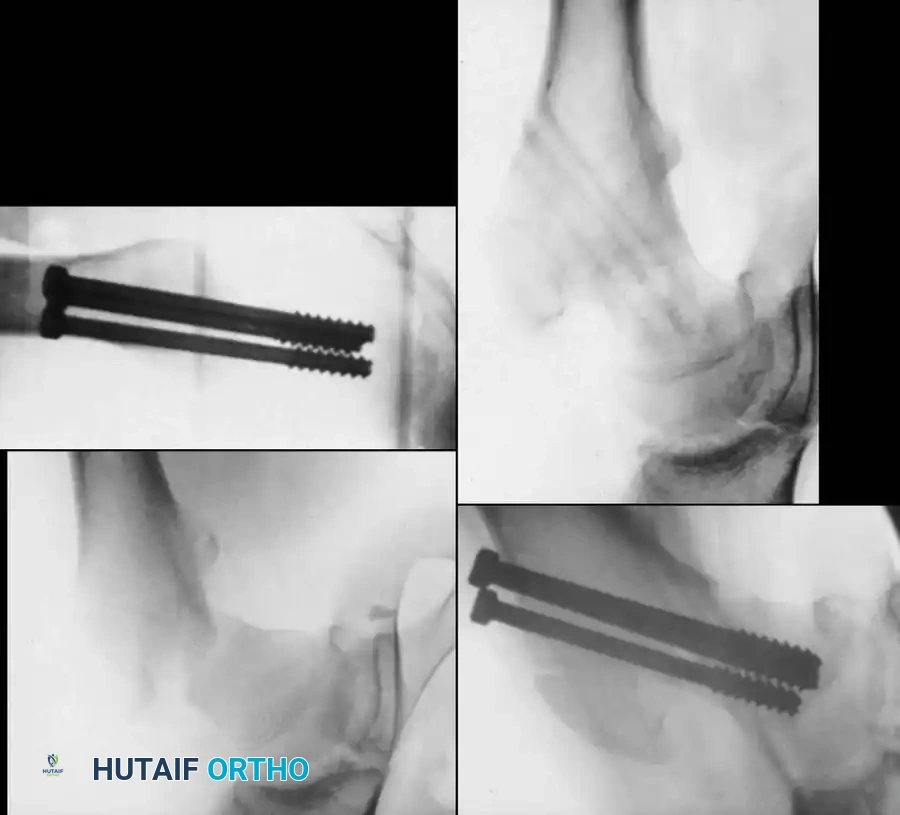

Management of Type II: Transcervical Fractures

Type II fractures are highly unstable. Even seemingly nondisplaced fractures will drift into coxa vara if treated with a spica cast alone.

- Positioning: Place the patient supine on a radiolucent flat table or a pediatric fracture table.

- Reduction: Perform a gentle closed reduction using longitudinal traction, abduction, and internal rotation. Verify anatomic alignment on AP and lateral fluoroscopy.

- Capsular Decompression: If closed reduction is achieved, perform a percutaneous capsular aspiration or a limited (1-2 cm) arthrotomy to evacuate the hematoma.

- Fixation:

- Use two or three partially threaded cannulated screws (typically 4.5 mm or 6.5 mm depending on the child's size).

- Crucial Step: The pediatric femoral neck is extremely hard. You must overdrill the near cortex to achieve a lag effect and prevent fracture distraction.

- Stop the threads short of the physis to prevent growth arrest. Do not use adult triflanged nails, as the impaction force will distract the fracture or separate the physis.

Fig. 11: Transcervical fracture stabilized with cannulated screws stopping short of the capital femoral physis.

Fig. 12: Lateral fluoroscopic view confirming central placement of the screws within the femoral neck.